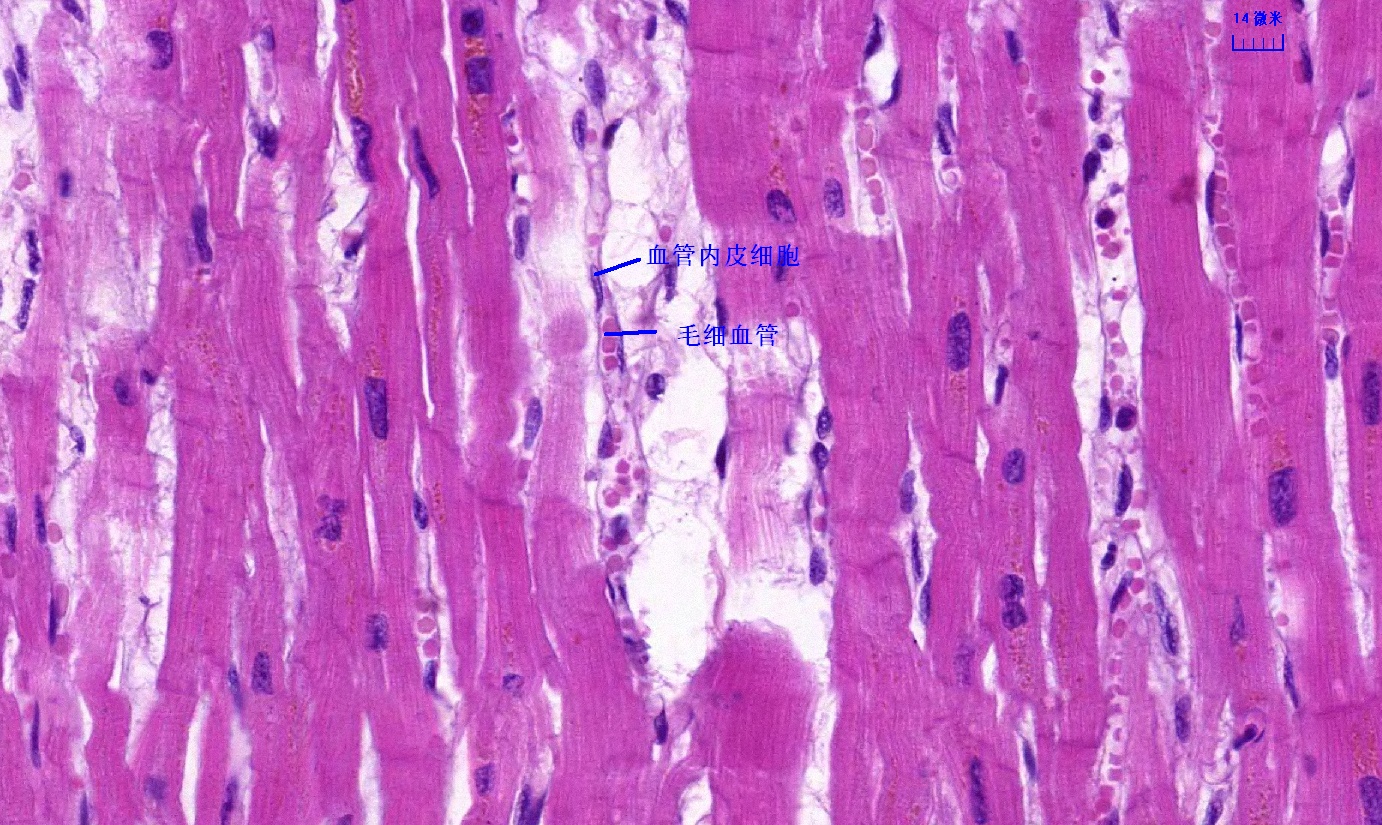

6 第六单元 循环系统

6.1 循环系统切片库

6.2 循环系统微课

6.3 循环系统课件